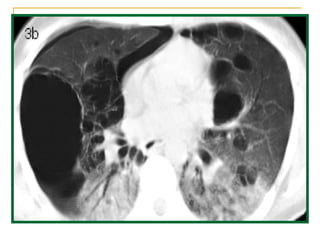

Historia Clínica Paciente de 36 años de edad, HIV (+), homosexual, sin tratamiento retroviral, sin profilaxis antibiótica, antecedentes de haber sufrido 4 episodios de neumonía, uno con derrame pleural. Una semana antes de su ingreso consultó por tos irritativa, fiebre, calofríos, dolor en el centro del tórax y disnea progresiva. Al ingreso, se encontraba polipneico, hipotenso, afebril Al examen físico existía candidiasis oral y crepitaciones en ambos campos pulmonares. El hemograma mostró anemia, leucopenia, Linfocitos T CD4 23%  Se efectuó fibrobroncoscopía con lavado broncoalveolar, que mostró tinción y PCR positivas para  Pneumocystis carinii.

Extenso enfisema buloso en los lóbulos superiores de ambos pulmones.

Hacia las bases hay aumento de la densidad radiológica

En la base derecha se observan imágenes quísticas